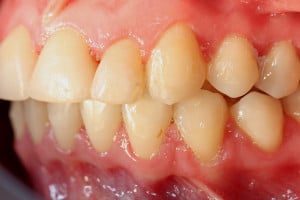

Młoda pacjentka zgłosiła się do naszego gabinetu celem wykonania kompleksowego leczenia zachowawczo-ortodontycznego. Oprócz problemów natury ortodontycznej stwierdzono złą higienę jamy ustnej oraz liczne potrzeby leczenia zachowawczo-endodontycznego. Po wnikliwej analizie telerentgenowskiej oraz analizie modeli zadecydowano o ekstrakcji 2 zębów w łuku dolnym (kła po stronie lewej oraz pierwszego przedtrzonowca po stronie prawej). Plan leczenia obejmował ponadto zamknięcie łuku po brakujących zębach w łuku górnym. Leczenie aktywne trwało 2 lata i 8 miesięcy. W czasie jego trwania pacjentka była regularnie poddawana zabiegom higieny profesjonalnej celem eliminacji zapaleń przyzębia brzeżnego. Po leczeniu aktywnym zastosowano leczenie retencyjne w postaci retainera stałego w żuchwie oraz szyny retencyjnej w łuku górnym.